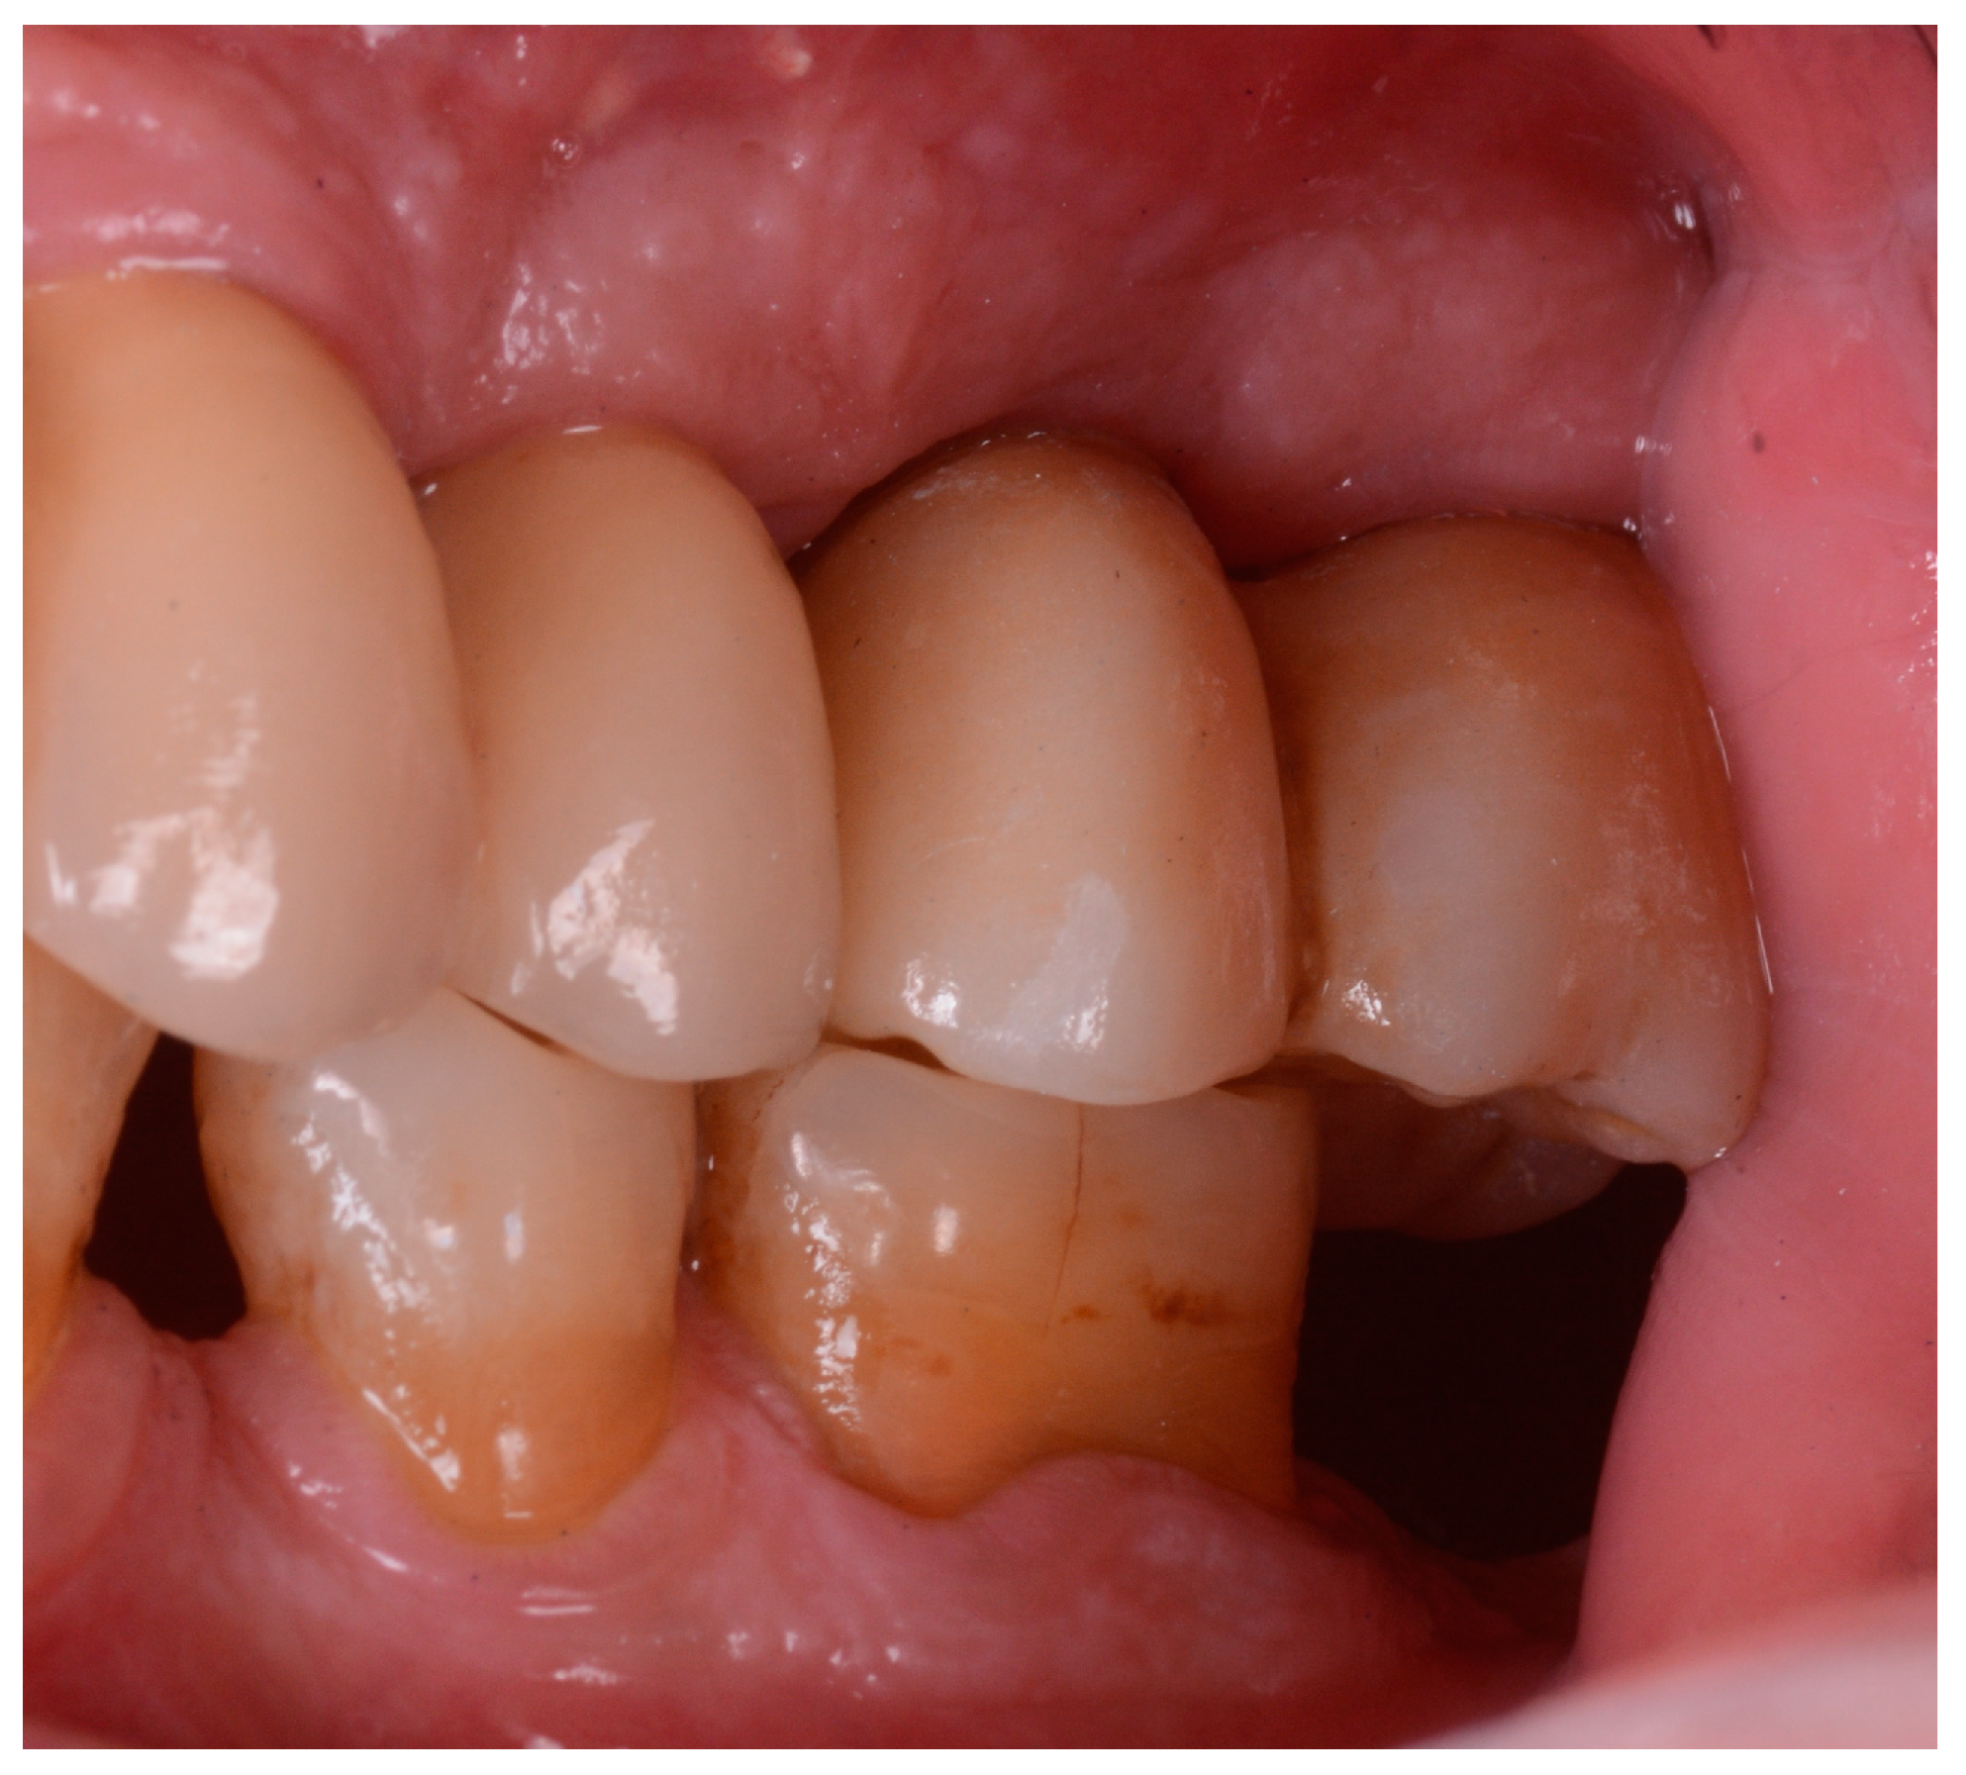

2.1. Implant Retrieval and Case Overview